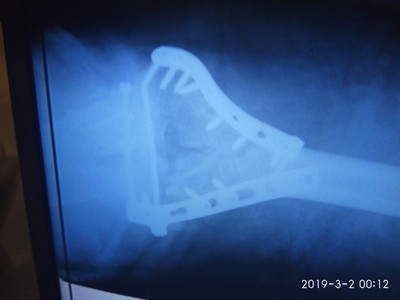

Кстати, снимок металлоконструкции после заживления:

Учитывая количество металла, я теперь немножко киборг. Или как сказала моя дорогая подруга, у всех мастеров руки золотые, а у меня золотые и усиленные титаном)